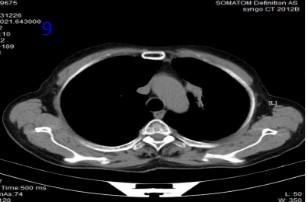

男性,61歲 ,因“確診左肺癌4月余,痰中帶血3天”入院?;颊哂?020年6月30日因"咳嗽、咳痰"在家人陪同下前往滕州某醫(yī)院行健康查體,行胸部CT提示左肺上葉占位性病變,左肺門及縱隔4R區(qū)可見腫大淋巴結(jié)(圖1)。2020年7月3日行CT引導(dǎo)下肺穿刺活檢,病理檢查示:(左肺穿刺活檢)分化差的癌,結(jié)合免疫組化結(jié)果考慮鱗狀細(xì)胞癌。免疫組化示:CK廣(+) CK5/6(+), P40(+),TF-1(-),CX7(-),CD56(-), NapsinA(-),CgA(-),Syn(-),Ki67(約50%陽性)。2020年7月-10月在外院完成“(白蛋白型)紫杉醇300mg,d1+洛鉑50mg,d1”化療3個周期,2020年10月20日復(fù)查胸部CT,腫瘤較前縮小,療效評價PR(圖2),患者因IV度骨髓抑制,嚴(yán)重乏力、納差未在繼續(xù)化療。近3日患者出現(xiàn)咳嗽,痰中帶血3天,病人為求進(jìn)一步治療到我院就診,門診以“左肺癌”收入院?;颊呶鼰?0年,20支/日,偶爾飲酒。既往史、婚育史、家族史無特殊。

圖1胸部CT:左肺腫瘤及腫大淋巴結(jié)

圖2 胸部CT可見腫瘤經(jīng)化療后減小